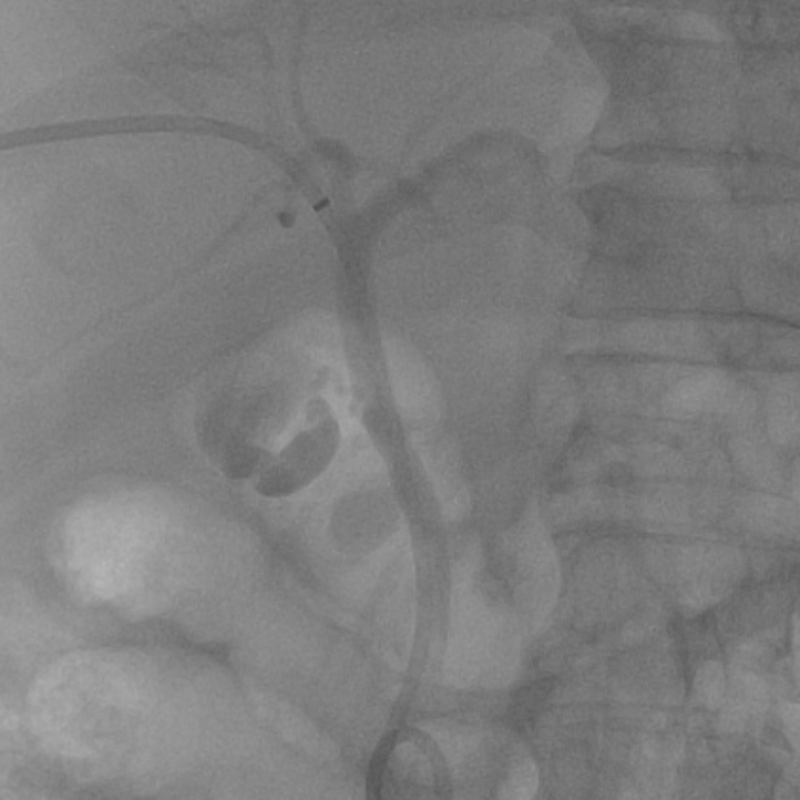

2023年10月28日,李大爺前往我院就診,經過醫生耐心詢問,得知李大爺上腹部疼痛劇烈,伴腹脹、嘔吐,既往有糖尿病病史及高血壓病病史。化驗結果顯示:血淀粉酶3755 U/L,血脂肪酶2537 U/L,尿淀粉酶10298 U/L。血總膽紅素108.8 umol/L,直接膽紅素54.19 umol/L,間接膽紅素54.61 umol/L。CT平掃檢查:膽總管下段結石(大小約12mm×9mm)伴肝內外膽管擴張,膽囊腫大,急性胰腺炎,腹腔積液,胸腔積液。

入院診斷出李大爺患有急性胰腺炎,膽總管結石伴急性化膿性梗阻性膽管炎,2型糖尿病,高血壓病。

在治療24小時后,李大爺突然病情加重,腹痛腹脹加重,腹部壓痛反跳痛加重,發熱體溫38℃,心率快達130次/分,呼吸35次/分,胸悶,血氧飽和度85%,血壓不穩定。復查血鈣降低1.89 mmol/L,血膽紅素升高,總膽紅素173.36 umol/L,直接膽紅素87.13 umol/L,間接膽紅素86.23 umol/L。李大爺表現為重癥急性胰腺炎伴膽道有梗阻及化膿性膽管炎,并有繼續惡化趨勢。

情況緊急,普通外科團隊第一時間進行術前病情討論,經過反復論證,普通外科團隊立即給予在插管全麻下行經皮經肝膽管穿刺置管引流術(PTCD)。